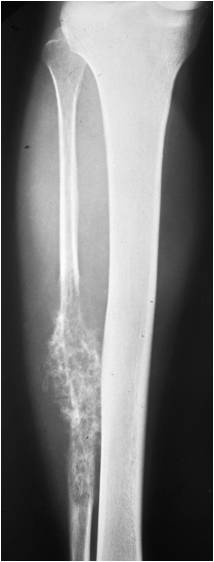

Radiographic Presentation

- Aggressive motheaten to permeative lesion

- Indistinct border in most cases

- Osseous destruction with a soft tissue component

- Chondroid matrix calcification may be present (60-70% of cases)

- Soft tissue mass